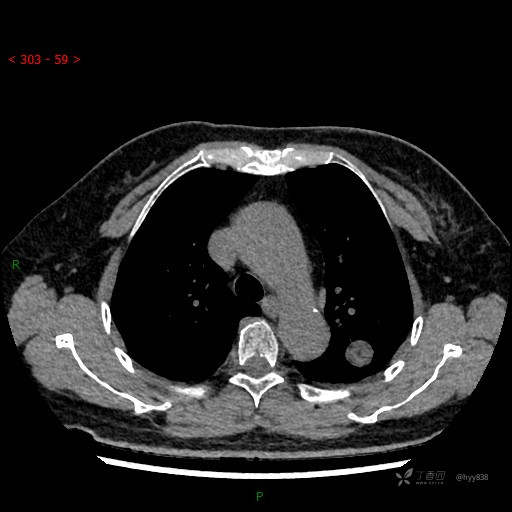

胸部CT平扫

各期CT值:28hu、58hu、69hu